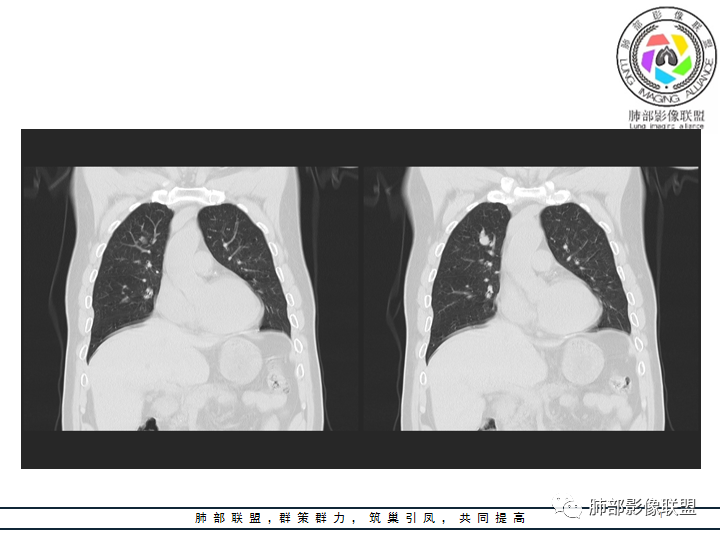

影像资料

老年男性患者,长期吸烟史,没有呼吸系统临床表现。胸部CT示右肺上叶实性密度结节影,密度均匀,未见空洞及钙化,边缘较光整,未见分叶及毛刺。血管影旁现侧出,支气管进入并截断,不均匀强化。